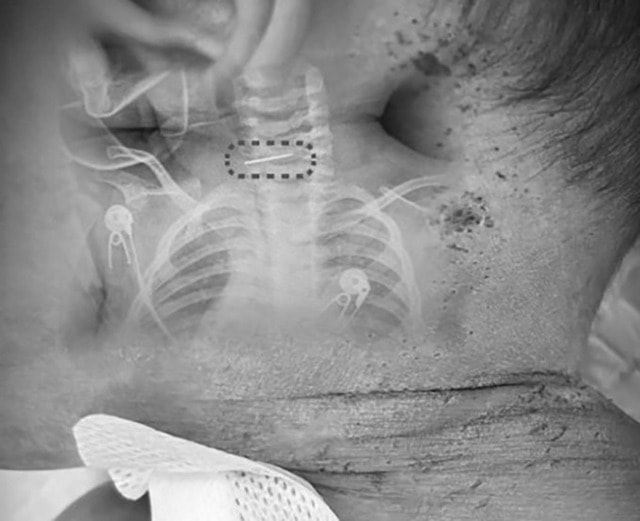

Tiếp nhận bệnh nhi trong tình trạng sốt cao, các bác sĩ phát hiện bé có nhiều vết kim đâm khắp cơ thể. Ngoài ra còn có một cây kim khâu giày gãy đôi, mắc kẹt sâu trong đốt sống cổ.

Theo báo cáo của SCMP, bác sĩ Sui ước tính đứa trẻ đã bị đâm khoảng 600 lần. Hình ảnh được ghi lại cho thấy nhiều vết đâm và các mảng vảy sẫm màu xuất hiện khắp bàn chân, đầu và thân mình của bé trai.

Bác sĩ Sui cho biết ca phẫu thuật gặp nhiều khó khăn do cha mẹ không xác định được hình dạng chính xác của cây kim, cũng như việc kim có ngạnh hay không. Việc rút kim sai hướng có thể khiến đầu kim móc vào các mô khác và gây tổn thương nghiêm trọng.